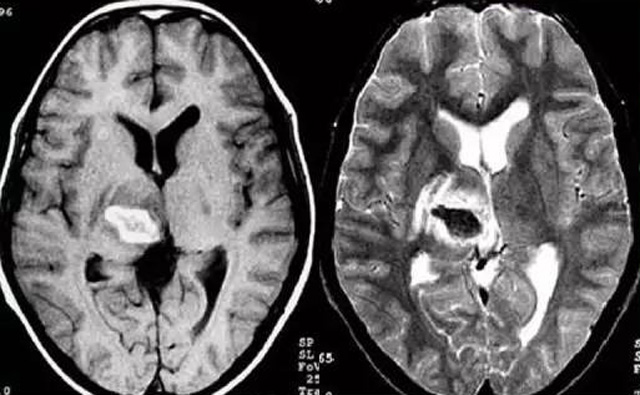

發(fā)現(xiàn)病人出血腦梗相關(guān)癥狀時候第一時間就醫(yī),需要攜帶以往的影像檢查資料。向醫(yī)生提供相關(guān)的病史基本資料。做影像檢查時候需要全身不攜帶金屬物品。檢查時候身體保持不動,不然偽影對檢查結(jié)果有干擾。磁共振MRI發(fā)現(xiàn)缺血性卒中后,幫助進(jìn)一步查找病因。由于CT上小腦跟腦干顱骨影響,容易導(dǎo)致漏診。MRI檢查可以對CT檢查不足的補充。短暫的腦缺血TIA也需要進(jìn)行影像檢查。短暫性缺血一般10幾分鐘后好轉(zhuǎn)。檢查目的可以確定TIA的病因。降低腦梗死的發(fā)生率。磁共振有助于排出TIA表現(xiàn)的顱內(nèi)病變,有診斷及時治療的價值。磁共振MRI檢查時間比較長,不太適合急診病人。但是可以發(fā)現(xiàn)腦干小腦的出血問題。因為急性腦梗死的早期和急性期,缺血區(qū)的腦組織還沒有完全壞死,頭顱CT不能顯示病灶,所以就需要MRI磁共振檢查,這個對陳舊跟亞急性出血顯示比較好。缺點性價比不高,費用比較貴。頭顱的磁共振MRI在發(fā)病后的幾天CT的敏感降低時候發(fā)揮大作用。,MRI可作為診斷蛛網(wǎng)膜下腔出血和了解破裂動脈瘤部位的一種重要方法,必要時進(jìn)一步進(jìn)行DSA檢查,幫助制訂臨床的手術(shù)治療方案,